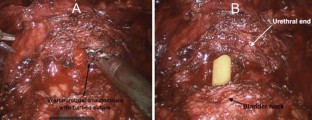

Fig. 2